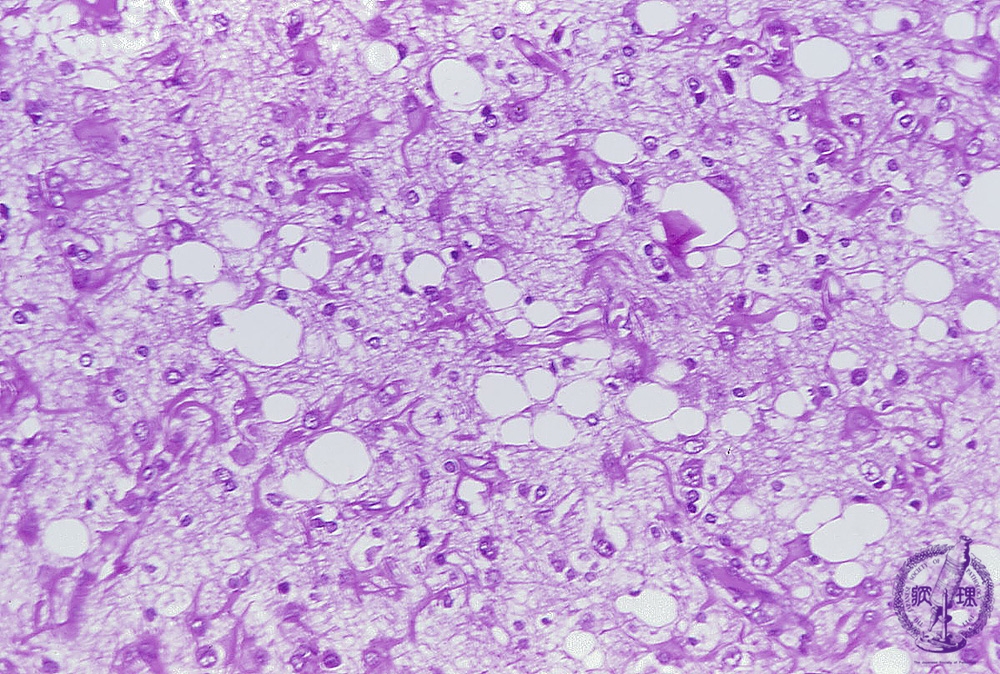

- (6)Creutfeldt-Jacob disease

Microscopic findings (H.E. high magnification) Various-sized vacuolation (spongiosis) was extensively detected in the cortex following loss of neurons, so that the disease was also termed as spongiform encephalopathy. Proliferation of glial cells is also apparent.